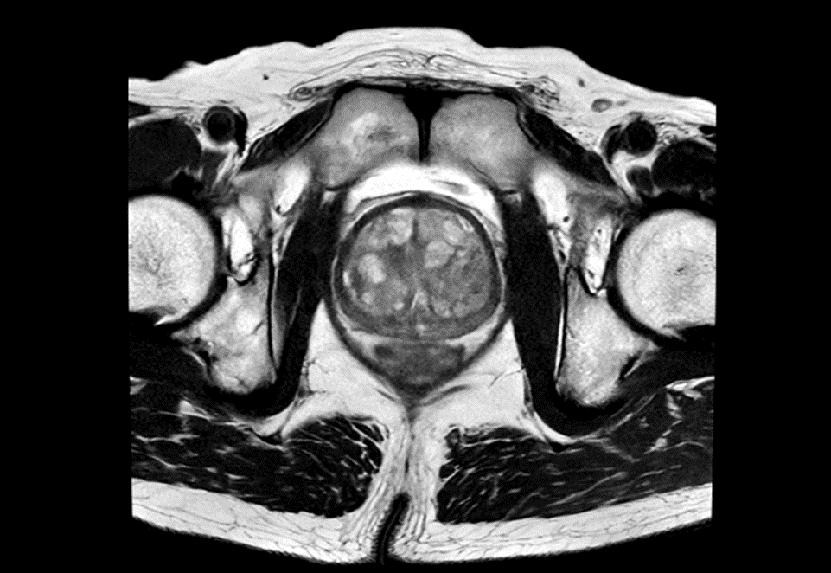

前立腺マルチパラメトリックMRIの撮像条件や読影方法の標準化を目的として、Prostate Imaging and Reporting and Data System (以下PI-RADS) が提唱されている。PI-RADSが求めているT2強調像の分解能は、面内0.4×0.7mm以下、スライス厚3.0mm以下という高分解能が要求されるため、1.5T装置では十分なSNRを担保することが難しく、検査時間の都合上、それに準拠したシーケンスを組むことは容易ではなかった。しかし、AIR™ Recon DLにより空間分解能とSNRの向上の両立に加え、撮像時間の短縮が可能となるため、当院でもPI-RADS推奨条件下での検査を行うことができようになった(図7)。読影レポートにもPI-RADSカテゴリーが記載されるようになり、基幹病院への不要な紹介が減ることで患者の身体的・精神的な負担を軽減できるだけでなく、医師にも有益な情報を提供できている。

Prime_Tamaki_09.png

図7 PI-RADSに準拠した前立腺T2強調像

空間分解能:0.4×0.7×3mm 撮像時間:2:24min